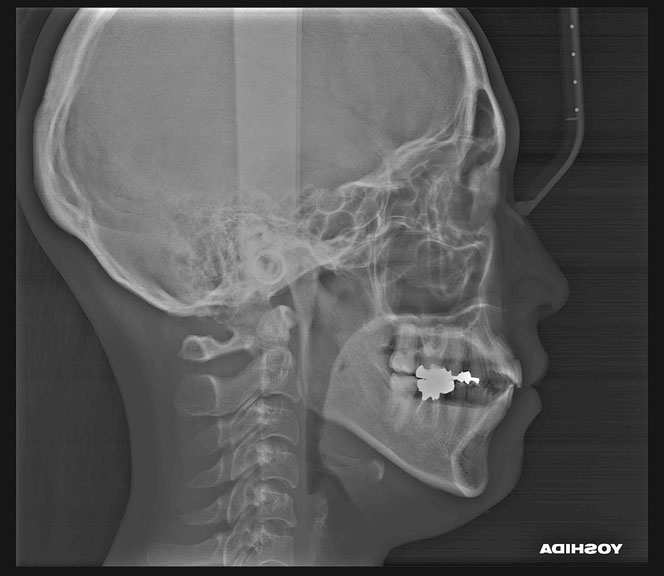

治療後の変化

再生治療により、

2~3ミリ下がっていた歯ぐきが回復。

歯の長さが自然なバランスに戻り、

厚みのある丈夫な歯ぐきが再建されました。

奥歯6本の再生治療を行ったケースでは、

虫歯予防という機能面の改善も期待できます。